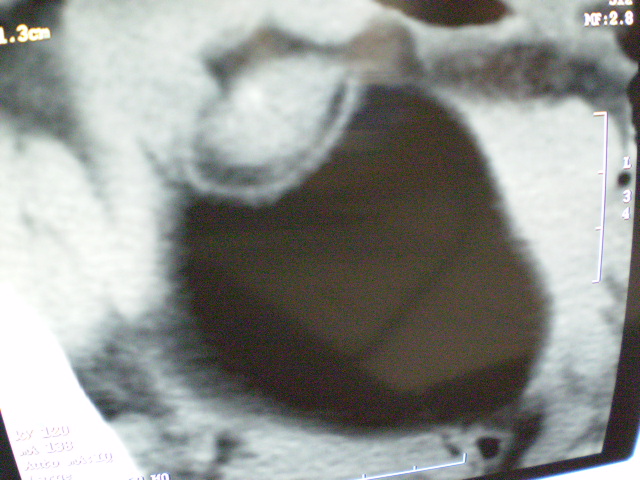

f 60y,b超提示脂肪瘤.[img][/img]

右侧附件囊性畸胎瘤,三种组织均见.

右侧附件囊性畸胎瘤.

那个高密度灶形状好象牙齿。典型,收藏了

脂肪密度肿块,内可见团块状影,典型皮样囊肿

的确比较典型的畸胎瘤!不过,应该确切的说是盆腔畸胎瘤,右侧附件来源的可能性比较大。